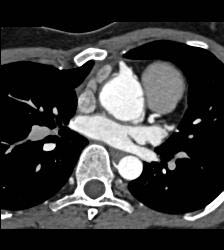

Dilated RCA After Reimplantation S/p Root Repair